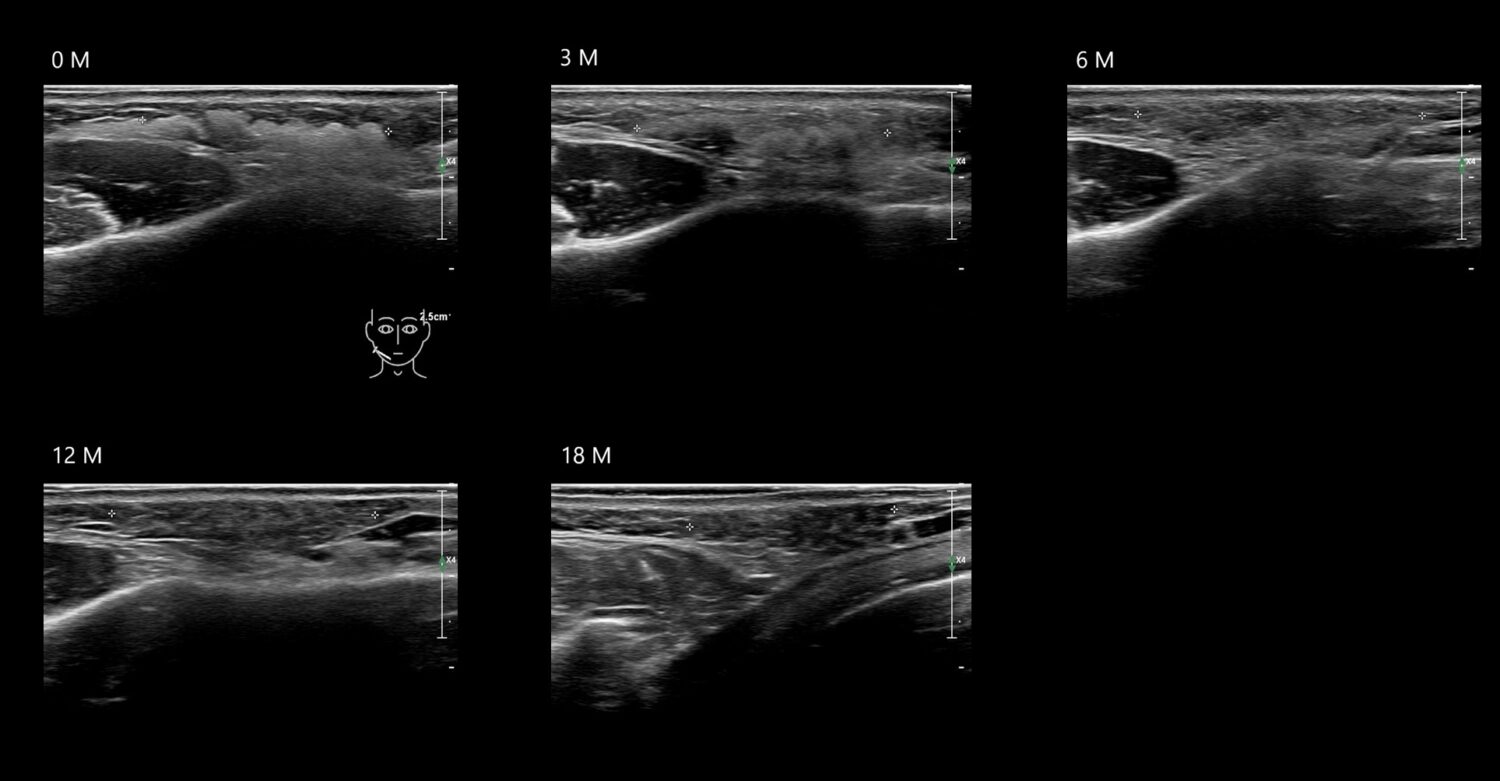

Fillers

Draw in the image on the right where the fillers are located. To check if your answer is correct, please click on the secondary image.